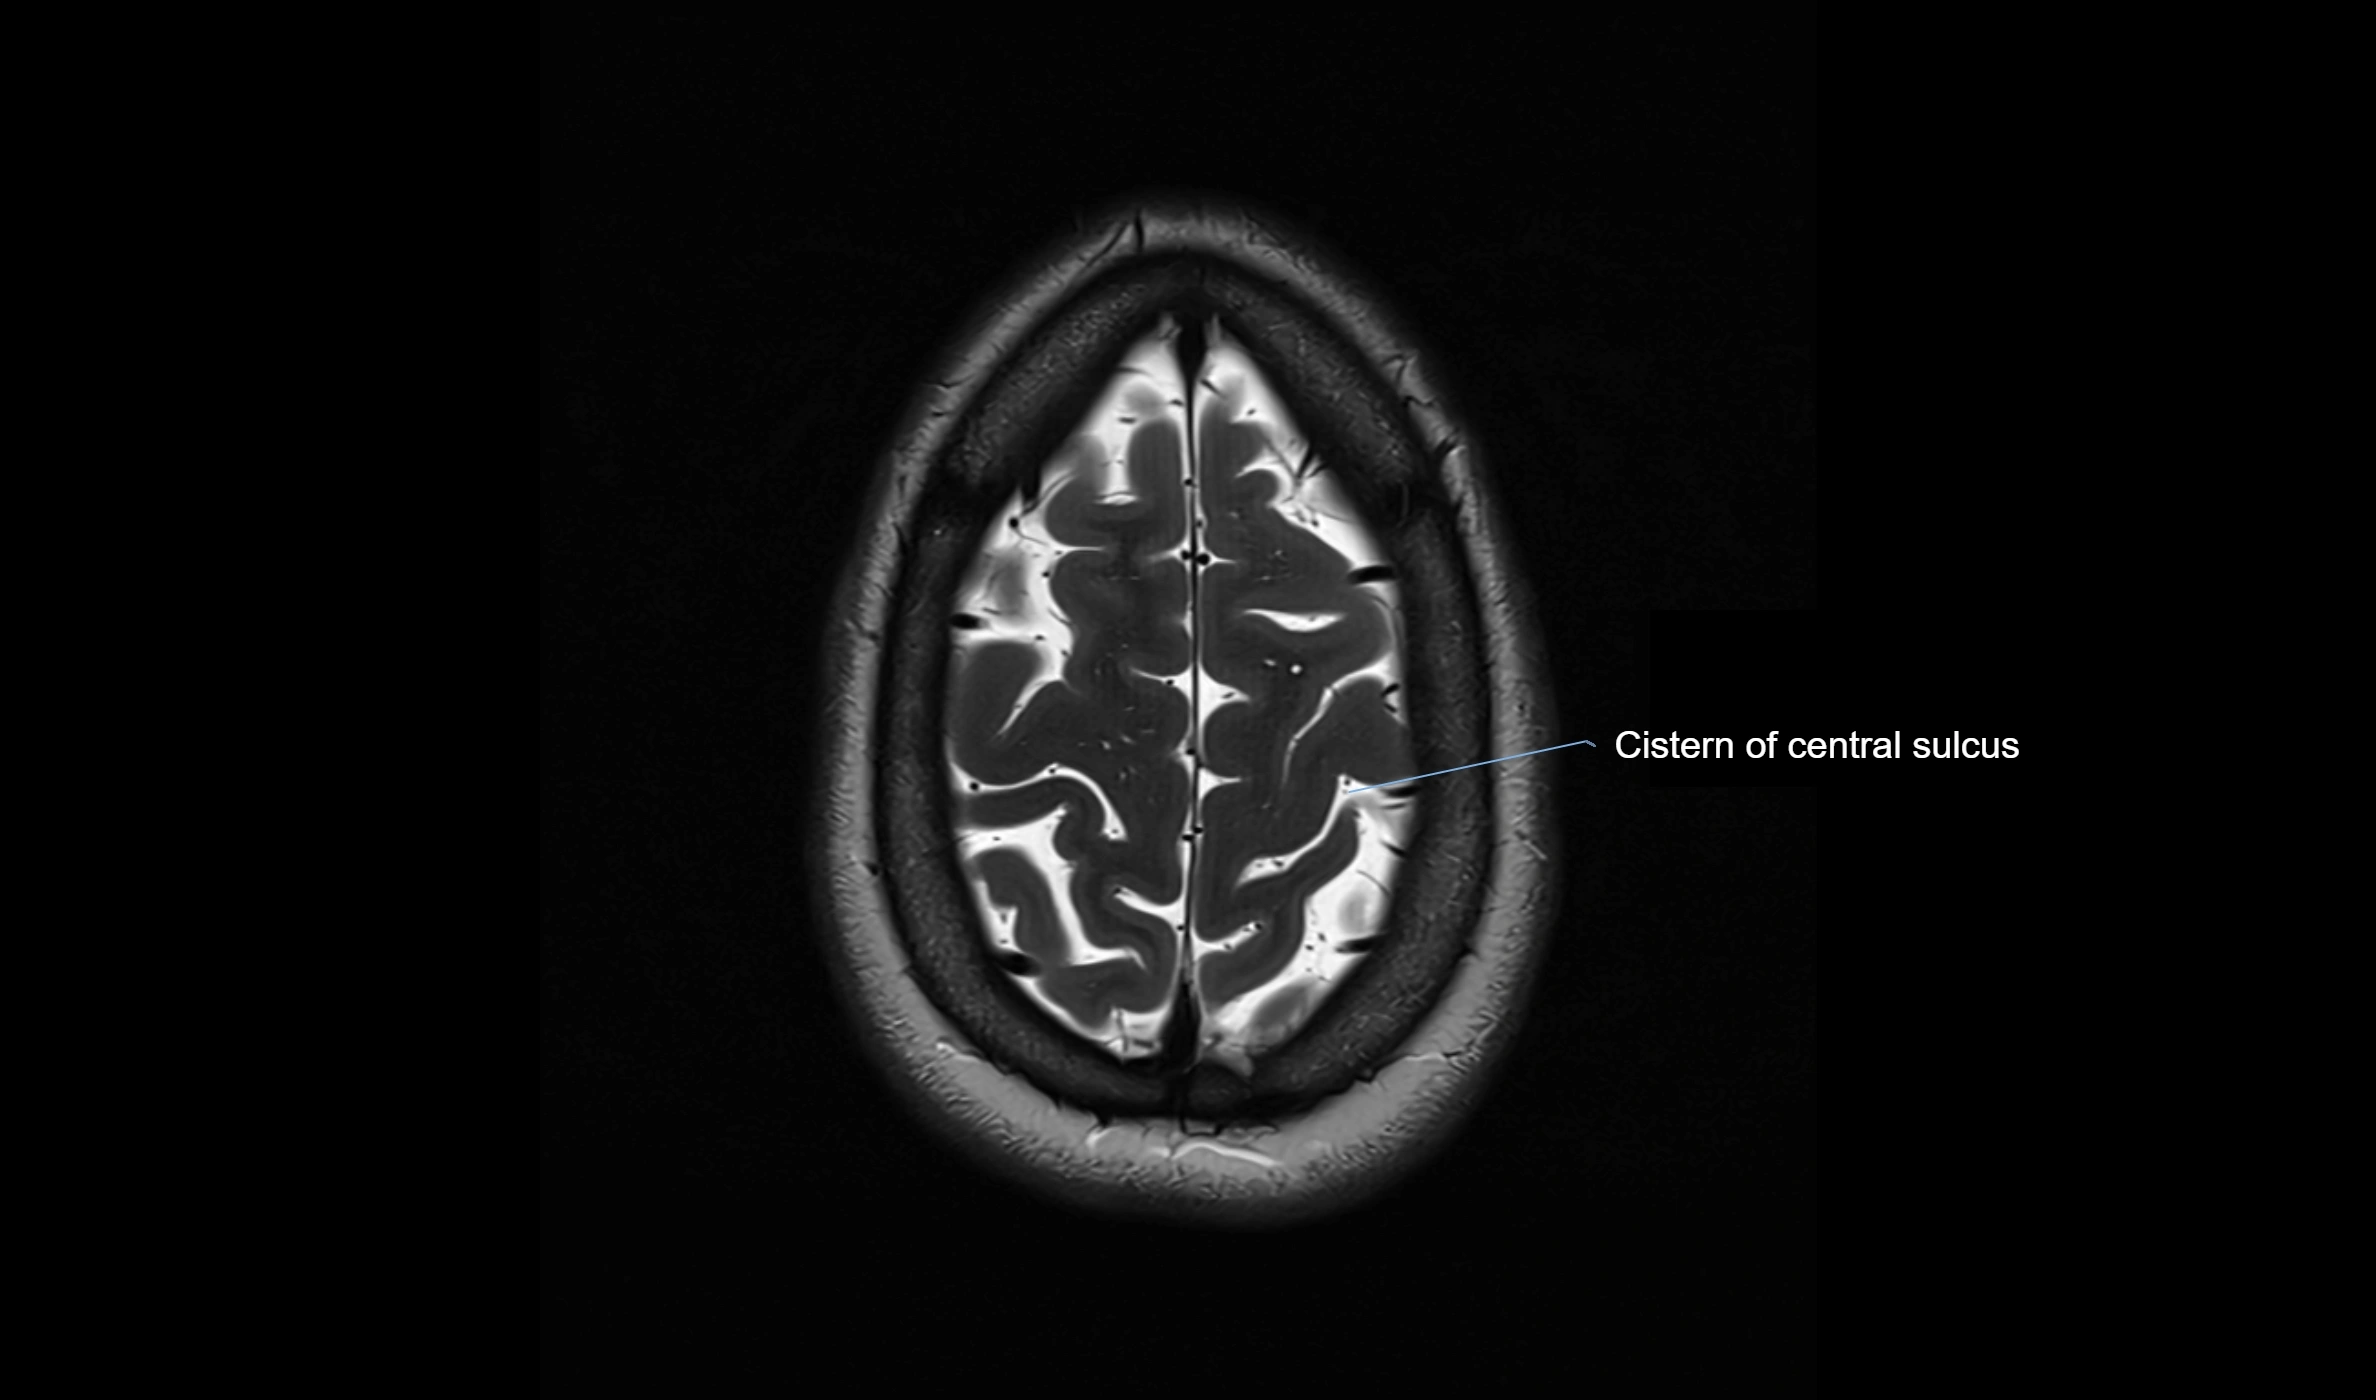

MRI images

image